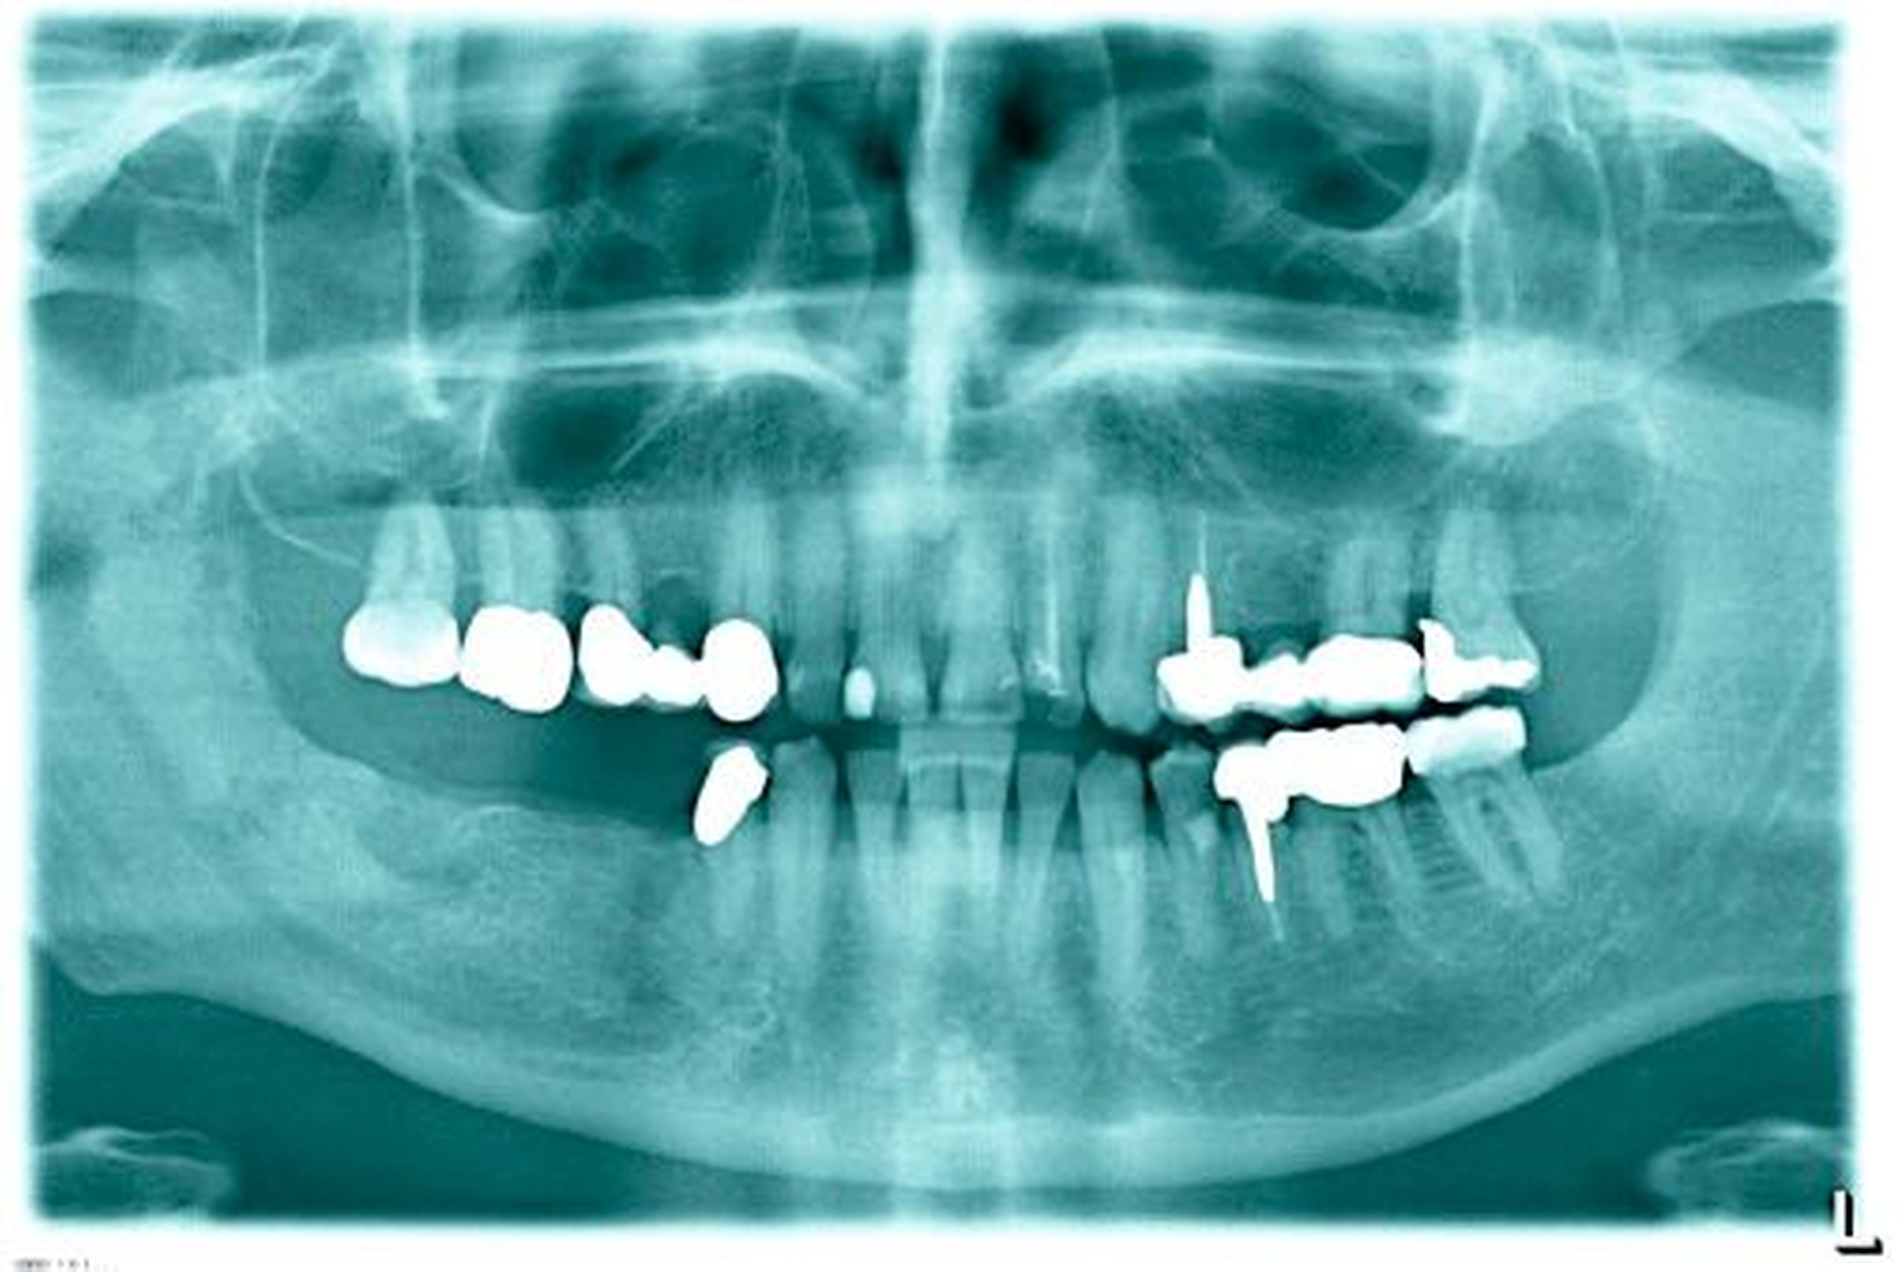

In einer erneuten Anamnese konnte eine einige Monate zuvor stattgehabte Extraktion der Zähne 47 und 45 verifiziert werden. Bei der klinischen Untersuchung fiel im Bereich 047 eine kleine Fistel auf, unter der sich Os palpieren ließ (Abbildung 3). In einer zum Zeitpunkt der Erstvorstellung bereits vorliegenden Panoramaschichtaufnahme (Abbildung 4) ist deutlich die veränderte knöcherne Struktur zu erkennen, mit verstärkter Sklerosierung distal der noch zu erkennenden Extraktionsalveole des Zahnes 47. Auf dem Weg zum Processus muscularis wird die starke Sklerosierung durch mottenfraßähnliche Osteolysezonen abgelöst.

Diagnostisch bietet sich zunächst die Panoramaschichtaufnahme an, wobei bei akuten Osteomyelitiden häufig wenig zu erkennen ist, da die osteolytischen Prozesse nicht weit genug fortgeschritten sind, als dass man etwas erkennen könnte. Es müssen lokal 30 bis 50 Prozent des mineralischen Anteils verloren gegangen sein, bevor sich dies im Röntgenbild niederschlägt. Weitere Optionen sind die Anfertigung von digitalen Volumentomogrammen, Computertomografien und Magnetresonanztomografien. Szintigrafien werden ebenfalls angefertigt, um die Aktivität der Entzündung abschätzen zu können und Sonderformen der Osteomyelitiden auszuschließen, bei denen mehrere Herde im Skelettsystem vorliegen wie bei der CRMO, der chronisch rekurrierenden, multifokalen Osteomyelitis [Baltensperger und Eyrich, 2009].